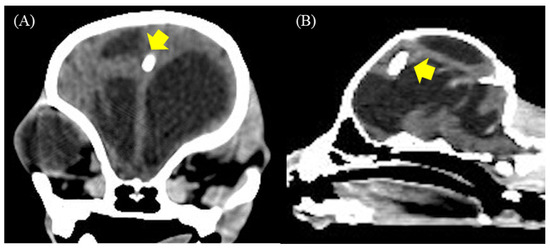

| 1 | Crossbreed | male | 2 | 2.4 | 3 | Mesencephalic aqueduct stenosis | 2.94 | 142.10 | 60 | 57.77 | Bilateral subdural hematoma and empyema |

| 2 | American Pitbull | male | 4 | 13.7 | 8 | Obstruction of interventricular foramen | 2.57 | 205.40 | 98.60 | 51.99 | Bilateral subdural hematoma and empyema |

| 3 | American Bully | male | 6 | 9.7 | 4 | Mesencephalic aqueduct stenosis | 3.68 | 139 | 7.57 | 94.55 | Bilateral subdural hematoma and empyema |

| 4 | Jack Russel Terrier | male | 6 | 1.6 | 12 | Mesencephalic aqueduct stenosis | 2.20 | 132 | 57.70 | 56.28 | Bilateral subdural hematoma |